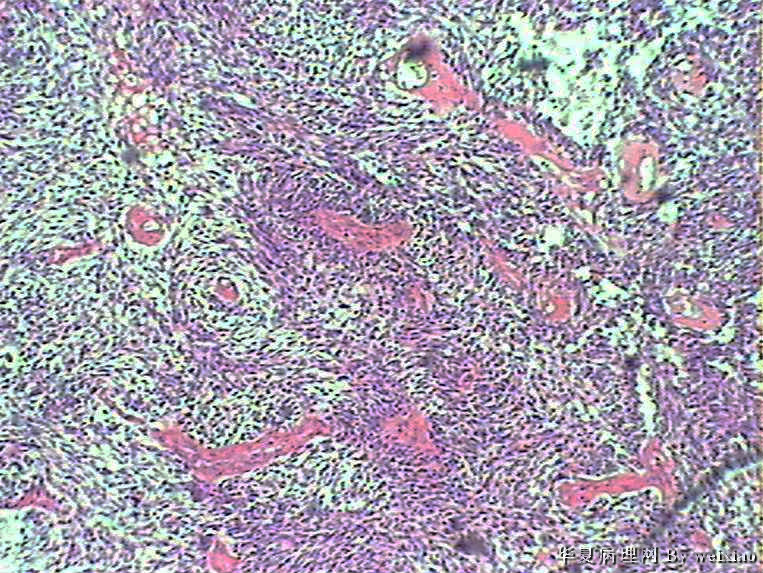

病史:男45岁,头痛2个月,手术所见:额叶占位性病变,与周围正常脑组  织的界限不清。

大体:灰白色碎组织一堆,质软,大小:2.5*1.8*1.3cm

• 额叶肿瘤图2

图2

×参考诊断

胶质母细胞瘤

The tumor cells are kind of spindle, need to rule out gliosarcoma, you need to check MRI films, do immunostain for GFAP, and vimentin. The vascular proliferation (VP) supports GBM.

肿瘤细胞呈梭形,血管增生明显,有坏死,符合胶质母。